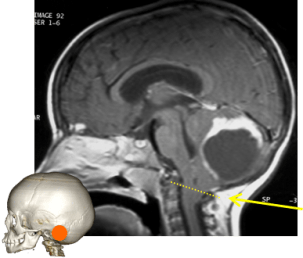

l’engagement du culmen

ou engagement rétrograde, survient quand une lésion du haut de la fosse postérieure s’engage vers le haut.

il est parfois favorisé par le drainage d’une l’hydrocéphalie sus-jacente.